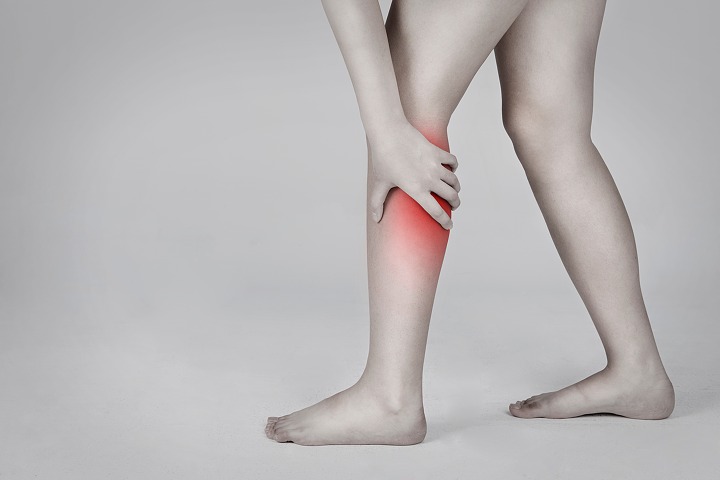

사건은 7년 전으로 거슬러 올라가는데, 임신 18주 차를 맞은 베키 터너는 다리에 알 수 없는 고통을 느껴 병원에서 검사를 받았으나 결과는 심각했다.

그녀가 어렸을 때부터 앓았던 선천성 척추갈림증의 영향으로 다리에 세균이 감염된 것이다.

세균을 죽이고 다리를 치료하려면 약을 복용해야 했는데 베키의 경우는 그렇게 할 수 없는 상황이었다.

임신을 하고 있었기 때문인데, 약으로 치료를 하면 세균뿐만 아니라 뱃속의 태아도 죽이기 때문이었다.

의사는 약을 먹고 다리를 치료할 것인지, 아기를 낳고 다리를 자를 것인지에 대해 물었으나, 베키는 고민하지 않고 아기를 낳겠다고 말했다.